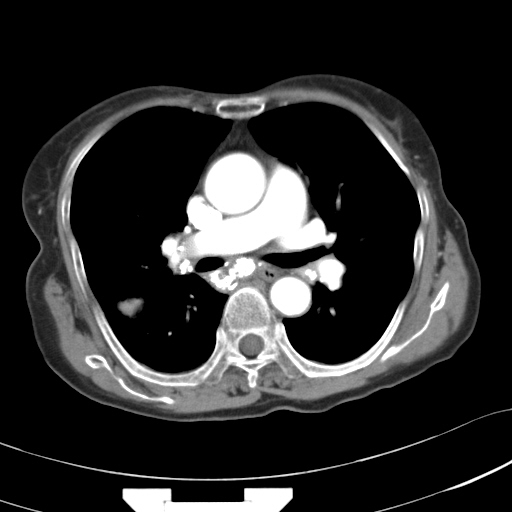

以下是引用hhcckk在2007-3-2 14:51:00的发言:[br]考虑结核球可能性大,依据[br]1病灶在下叶背段,结核的好发部位[br]2病灶内有大量的钙化,纵隔内有大量的淋巴结钙化[br]3重要的是半年前与现在相比无变化,假如是肿瘤的话不会这么‘善良’[br]4病灶周围卫星灶不明显,病灶有毛刺,胸膜凹陷,肿瘤不能完全排除,有条件的话最好做个活检

以下是引用liuyue在2007-3-2 17:15:00的发言:[br]1位置:右上叶后段[br]2性质:大分叶、粗长毛刺、条状斑片状钙化、纵隔多发淋巴结钙化,无强化,故考虑:肺结核灶(陈旧)